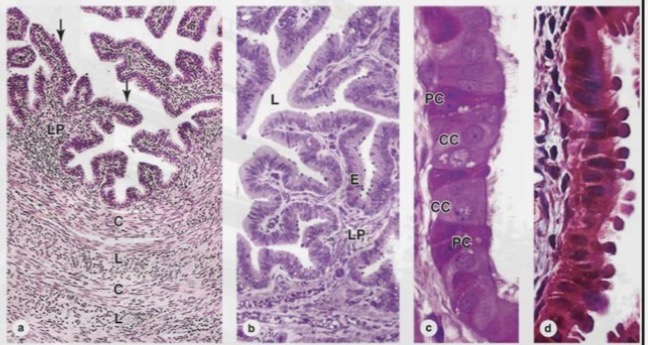

Uterine tube

Uterine tube microscopy

The wall consists of:

• Folded mucosa with

ciliated and secretory

cells

• Smooth muscle layer

for peristalsis

• Outer serosa